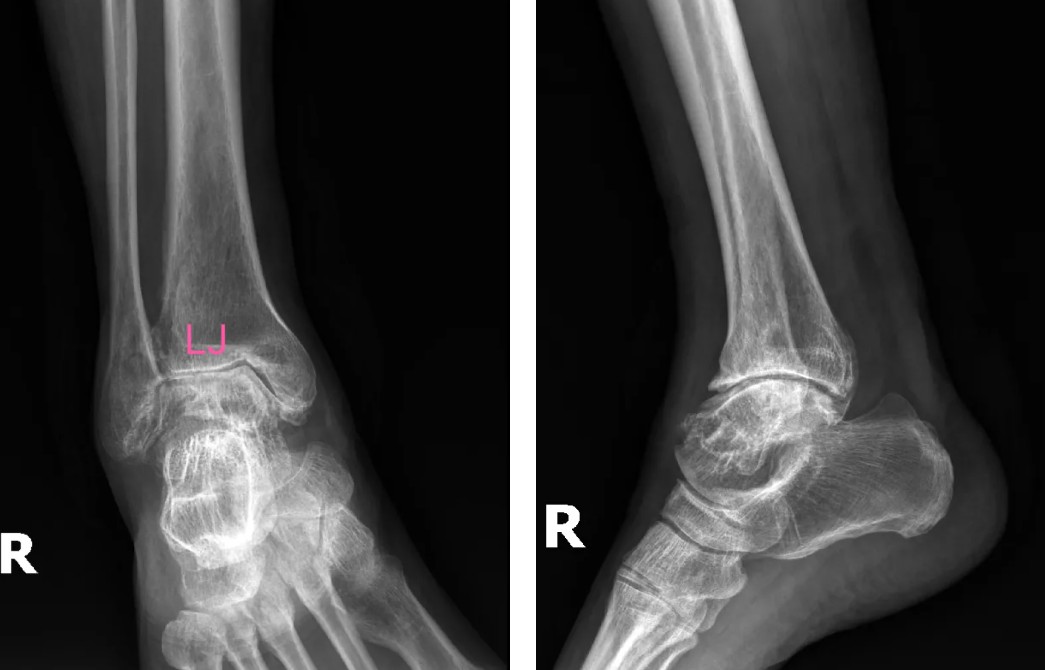

術(shù)前影像